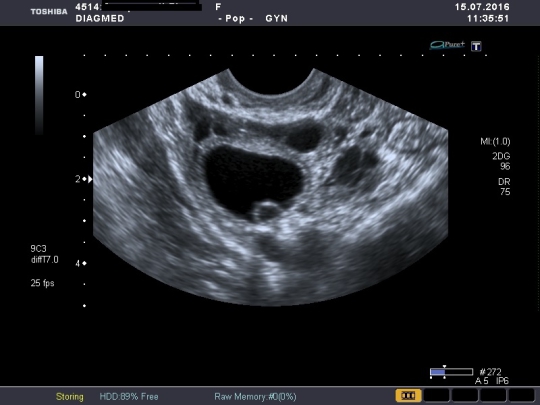

Желтое тело на УЗИ

Желтое тело можно обнаружить во время диагностической процедуры, если УЗИ пришлось на период сразу после овуляции. Это подтверждает, что цикл овуляторный и сама овуляция прошла нормально.

Желтое тело можно увидеть на трансабдоминальном и трансвагинальном УЗИ органов малого таза. Для женщин, живущих половой жизнью, более точным вариантом будет трансвагинальное исследование.

На экране аппарата врач УЗИ увидит неоднородное округлое образование. Появляется желтое тело в правом или левом яичнике в зависимости от локализации созревания доминантного фолликула и овуляторной яйцеклетки. Сторона созревания не имеет принципиального значения для будущей беременности и здоровья женщины.

Кроме того, из желтого тела иногда развивается киста — полостное образование с жидкостью внутри. Патология характеризуется частыми сбоями в ежемесячном цикле, тянущими болями внизу живота. Более подробно в ситуации должен разбираться опытный гинеколог.